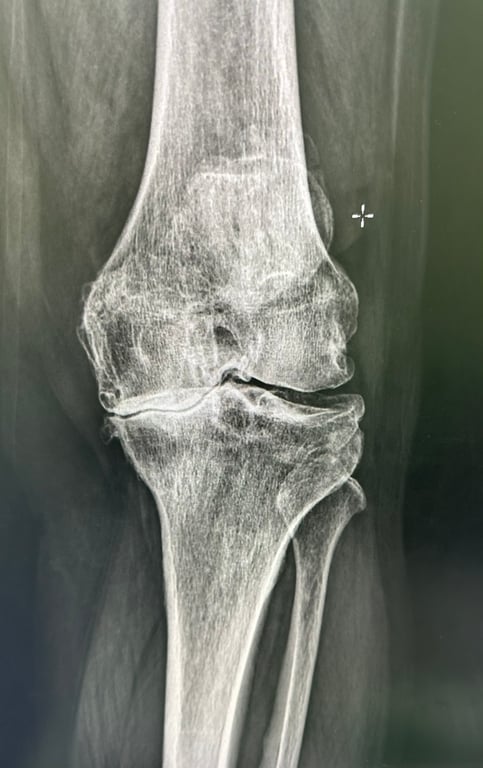

三期:嚴重退化

嚴重程度退化

關節軟骨大量流失,疼痛持續且加劇,明顯影響日常生活品質

X光影像

主要症狀

持續性膝蓋疼痛,休息時也會痛

關節明顯腫脹和發熱

活動時有明顯的咔咔聲或摩擦聲

治療建議

積極的疼痛管理和功能重建,可能需要侵入性治療

醫師會透過詳細的病史詢問、膝關節的理學檢查(觸診、活動度測試)來初步評估。X光檢查是診斷退化性膝關節炎最主要的影像工具,可以清楚看到關節間隙變窄、骨刺形成、軟骨下骨硬化等退化徵象。